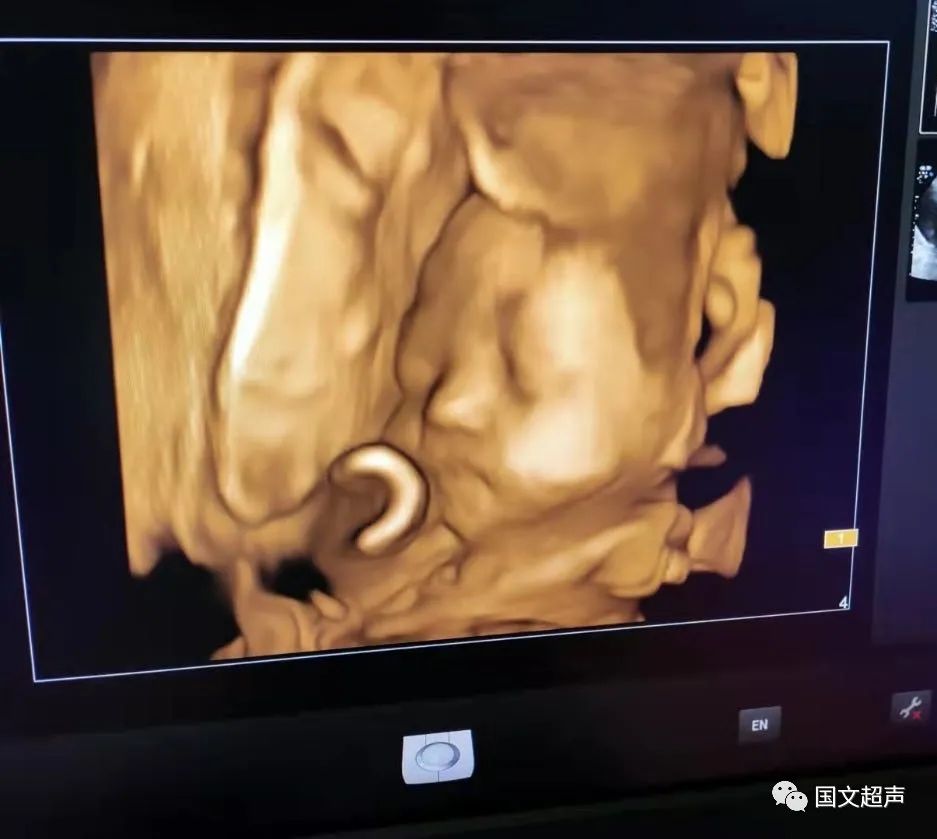

一.飛利浦EPIQ7高端四維彩超

我院目前使用的是飛利浦EPIQ7高端四維彩超,它擁有高品質(zhì)自動成像分析技術(shù),分辨率及清晰度高,可以較清晰的顯示宮內(nèi)胎兒的生長發(fā)育情況,為診斷胎兒先天性畸形,如唇裂、脊柱裂、顱腦發(fā)育異常、骨骼發(fā)育異常、心血管畸形等提供準(zhǔn)確的科學(xué)依據(jù)。

2.孕22周~26周,這個時期檢查,胎兒大小及羊水適中,胎兒活動度大,有利于觀察宮內(nèi)胎兒的生長發(fā)育情況,如果胎兒位置不好,也可以通過孕媽的走動改變胎兒體位,觀察到所需的留圖切面和四維圖像。